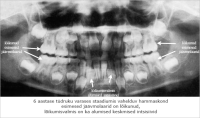

Katt ja igemepõletik

14